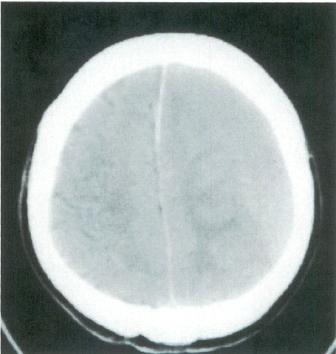

72歳の男性。頭痛を主訴に来院した。2か月前に家の中で転倒し,頭を打ったことがある。2週前から右上下肢の脱力感を自覚していたが,数日前から頭痛も自覚している。頭部単純CTを別に示す。

診断はどれか。

○ e

正解 e

診断 慢性硬膜下血腫

頭部単純CTを別に示す。

診断はどれか。

○ e

正解 e